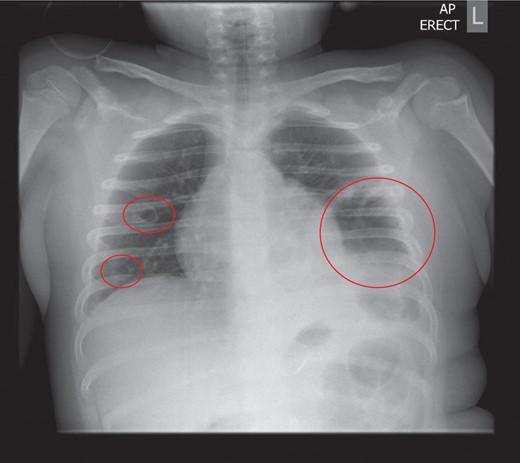

The initial chest radiograph revealed a possible diaphragmatic hernia and the patient was transferred to our institution for further investigation. The chest radiograph on arrival demonstrated a large air filled cavity at the left lung base. Further smaller cystic cavities were seen medially at the left base and right mid zone. The possible differential diagnoses included lung abscesses or diaphragmatic hernia (Fig. 1).

Chest radiograph on admission: a large air filled cavity at the left base. Further small cystic cavities seen medially at the left base and right mid to lower zone.